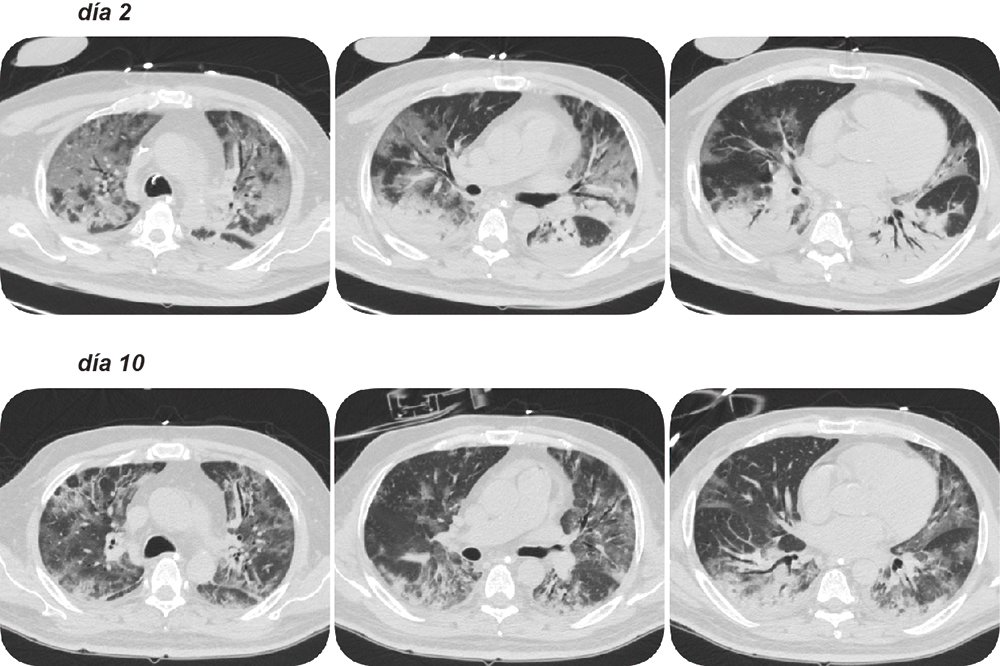

3) Imágenes

Las imágenes, en especial la tomografía computarizada, nos refleja con gran acuciosidad el estadío de la enfermedad, el grado de compromiso pulmonar, la presencia de enfermedad tromboembólica y otras complicaciones. En particular, una imagen en la segunda o tercera semana es fundamental para determinar el grado de organización, y decidir aportes adicionales de esteroides (figura). Sin embargo, la radiación ionizante es un tema que nos obliga a ser juiciosos y prudentes en su indicación.